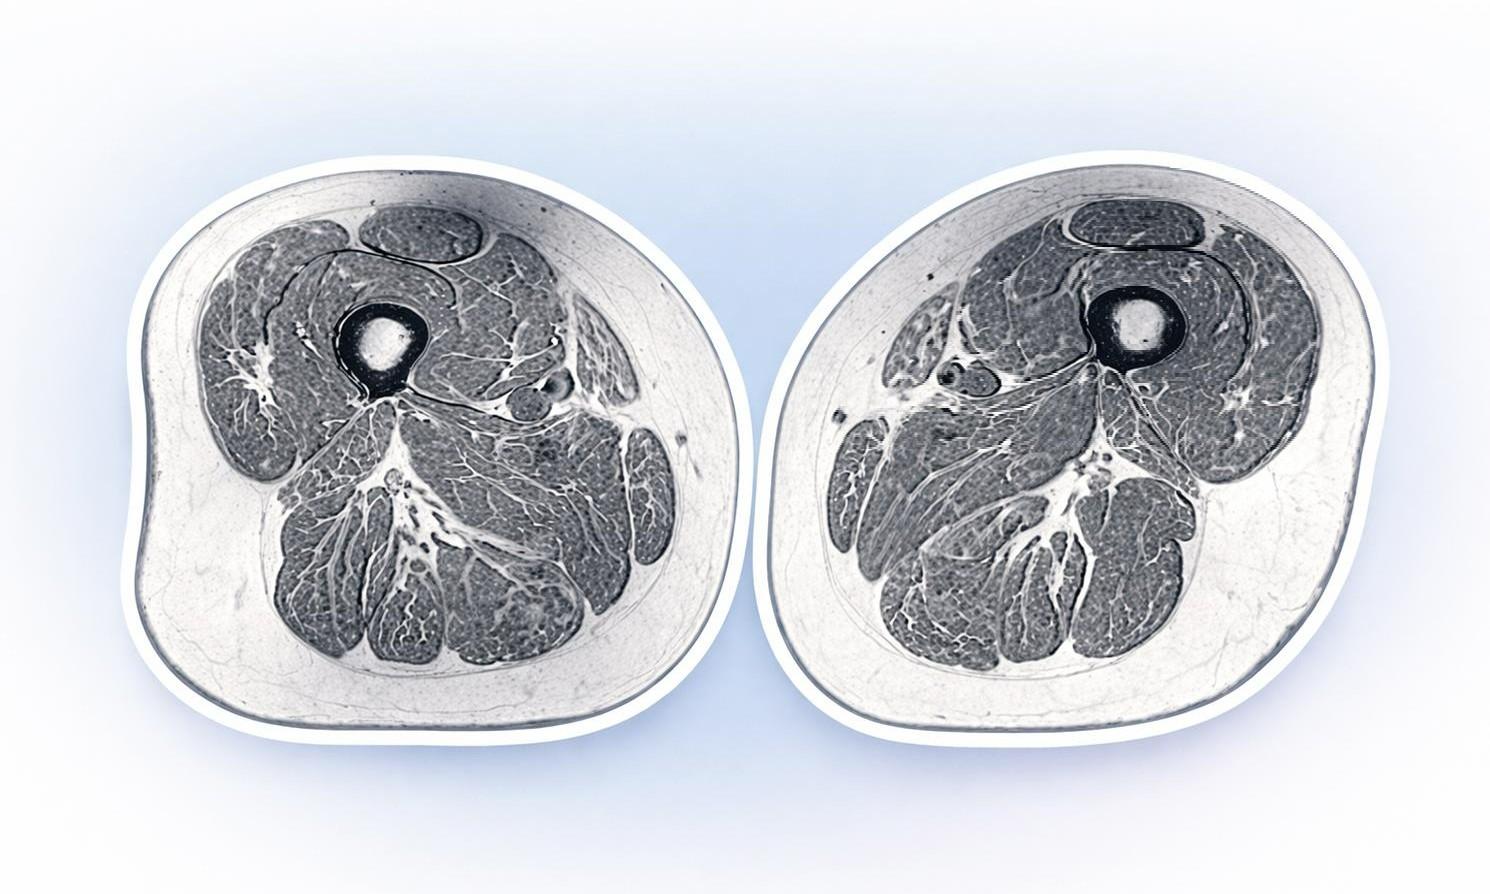

Изображение на МРТ-снимке бедра 62-летней женщины, которая в течение года 87% калорий получала из ультрапереработанных продуктов, выглядит как фото высококачественного стейка с ярко выраженной мраморной текстурой — обильными мелкозернистыми прожилками жира.

Прожилки жира, скрывающиеся между мышечными волокнами и внутри них, могут сигнализировать о серьезных проблемах со здоровьем, доктор Зехра Аккая из Калифорнийского университета в Сан-Франциско. Аккая — ведущий автор исследования, в котором анализировалось влияние ультрапереработанных продуктов на внутримышечный жир у людей, подверженных риску остеопороза коленного сустава.

Исследователи обнаружили, что чем больше ультрапереработанных продуктов потребляли люди, тем больше внутримышечного жира у них было в мышцах бедер, причем независимо от калорийности рациона и уровня физической активности. На МРТ можно увидеть, как жировую дегенерацию мышц, при которой полосы жира замещают мышечные волокна.